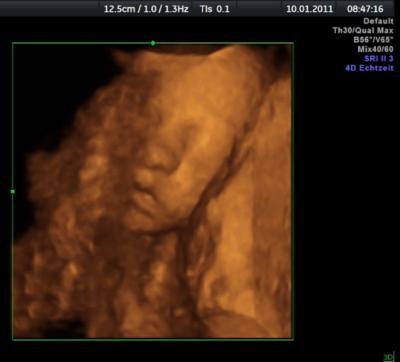

Tina28374

Das ist unsere Maus heute. Leider hatten wir dasselbe Problem wie Nini, dass nicht genug Fruchtwasser vorm Gesicht war und deshalb nur eine Hälfte zu sehen war. LG Tina